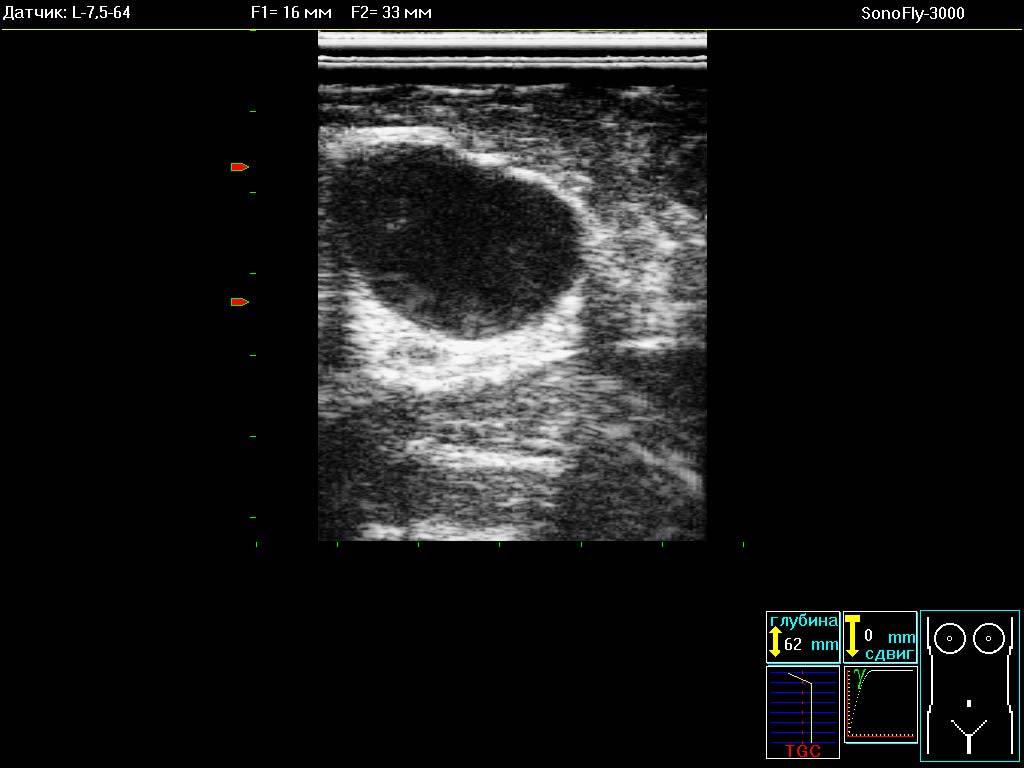

- Ультразвуковые УЗИ сканеры SonoFly